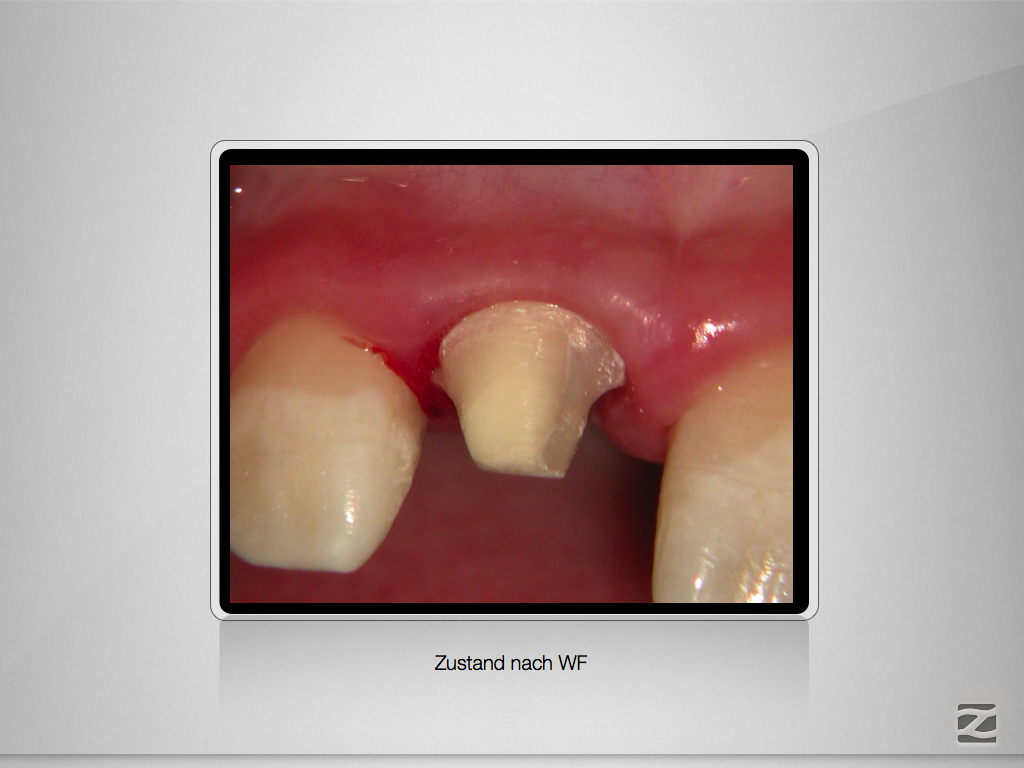

Komplizierte Kronen-Wurzelfraktur